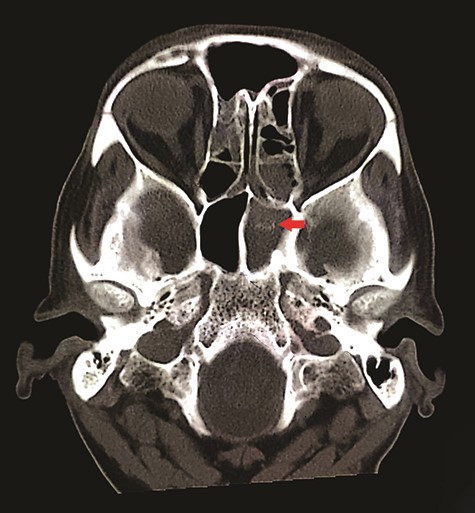

CT unveiled calcified densities within areas of hypoattenuation in the left sphenoid sinus. No marked bony destruction was observed (Fig. 2). A subsequent magnetic resonance imaging (MRI) was carried out to show hypodensity on T1 weighted post-contrast, and flow void in T2 weighted images within the same sinus (Figs. 3 and 4). Following informed consent, an emergency endoscopic left trans-ethmoidal sphenoidotomy was performed under general anaesthesia. A dense, darkened clay-like mass surrounded with the mucopurulent discharge was noticed within the left sphenoid sinus. The mucosa appeared inflamed and oedematous without clinical evidence of frank necrosis. The debris was utterly removed with a curette and sent for evaluation. The left sphenoid sinus was widened and thoroughly rinsed.

Axial view of non-contrasted CT bone window showed ‘double density’ sign within the left sphenoid sinus (red arrow); there was hyper attenuation observed in the centre of the sinus with surrounding mucosal thickening, suggestive of fungal concentration.